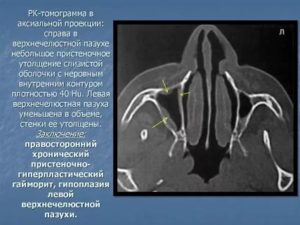

Гиперплазию эпителия можно заметить только на рентгеновских снимках. При подозрении на утолщение врач выдает направление на рентген, который позволит заметить даже минимальное увеличение эпителиального слоя в виде затемнения. Рентген также показывает наличие и уровень жидкости в синусах, а по ее расположению можно определить степень воспаления.